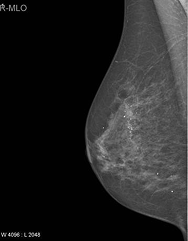

MLO Right

Right MLO Sample

MLO Right Grad-CAM